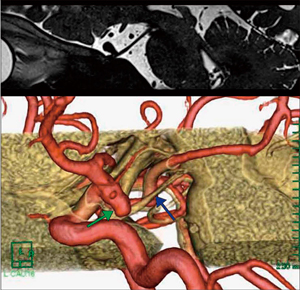

■症例2:微小血管減圧術(50歳代,女性)

左顔面痙攣と診断され,微小血管減圧術を予定し,術前検査を行った。同範囲のMRAとHeavy T2強調元画像を撮像し,それらをMulti Volume機能で重ね合わせてVR画像を作成した(図4)。VR画像はHeavy T2強調invert元画像(図5)に比べ,血管の走行を一目で把握でき,圧迫責任血管は後下小脳動脈であると推定できた。術野の角度に合わせた画像では,術中写真と同様の神経,血管走行が確認でき,微小血管減圧術の術前シミュレーションに有用であった(図6)。

図4 症例2:脳神経Multi Volume画像 |

図6 症例2:術中写真と脳神経Multi Volume画像の比較

顔面神経が聴神経の背面に走行している。

○圧迫部位 →後下小脳動脈 →顔面神経 →聴神経